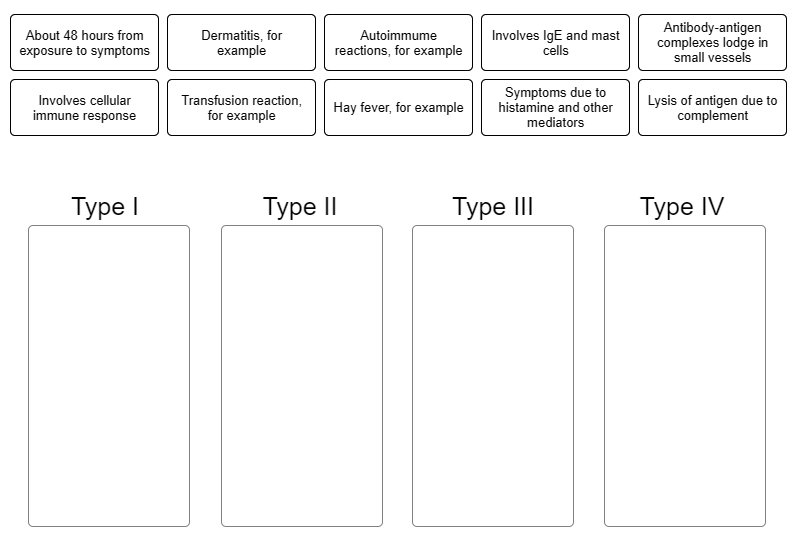

Indicate characteristic into the appropriate box, describing each type of hypersensitivity.

1. In antibody-dependent cytotoxic allergic reactions (type II), the

binding of __________ to targeted cells results in lysis of those

cells.

2. Which of the following transfusions would result in an

antibody-dependent cytotoxic (type II) allergic reaction?

1. Antibodies

2. Type A blood given to a type B recipient

1. Immune complexes that are not removed by macrophages can react

with and activate __________.

2. The degranulation of cells

called __________ occurs in response to the activation of complement

by immune complexes. The result is __________ of blood vessels. This

leads to some of the symptoms of a type III hypersensitivity

reaction.

3. 3. The presence of the immune complexes and

complement attracts and activates neutrophils, causing them to

degranulate. What is the effect of neutrophil activation? (This effect

will also lead to some of the symptoms of a type III response.)

1. Complement

2. Basophils; vasodilation

3. Tissue damage

1. Delayed hypersensitivity is __________ mediated.

2. What type

of cell is responsible for contact dermatitis and tissue

rejection?

3. In a reaction to poison oak or poison ivy, a small

molecule from the plant, called a(n) __________, will bind to a host

molecule, triggering an allergic reaction.

4. What is presented

on the macrophage surface?

5. First exposure to the allergen

(hapten) causes an increase in the number of __________.

6. What

attracts additional macrophages and causes their release of mediators

of inflammation?

1. Cell

2. Th1 cells

3. Hapten

4. Hapten plus class II

MHC

5. Th1 cells

6. Release of cytokines from Th1 cells